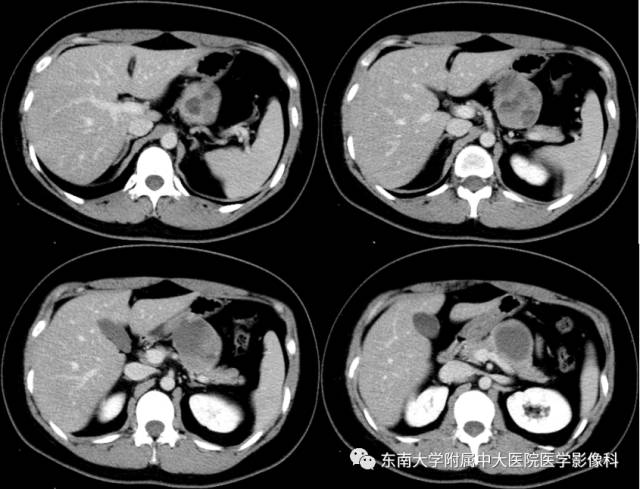

【病例】胰腺实性假乳状瘤1例CT影像表现

女,28岁,因“发现胰腺占位一月余”入院。肿瘤指标正常。

CT

平扫 增强